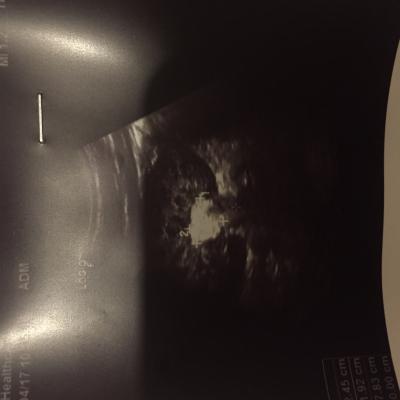

1) Показать ребенка урологу на очном приеме

2) Сделать анализ общеклинические анализы и биохимические анализы крови.

3) Сделать компьютерную томографию с контрастированием.